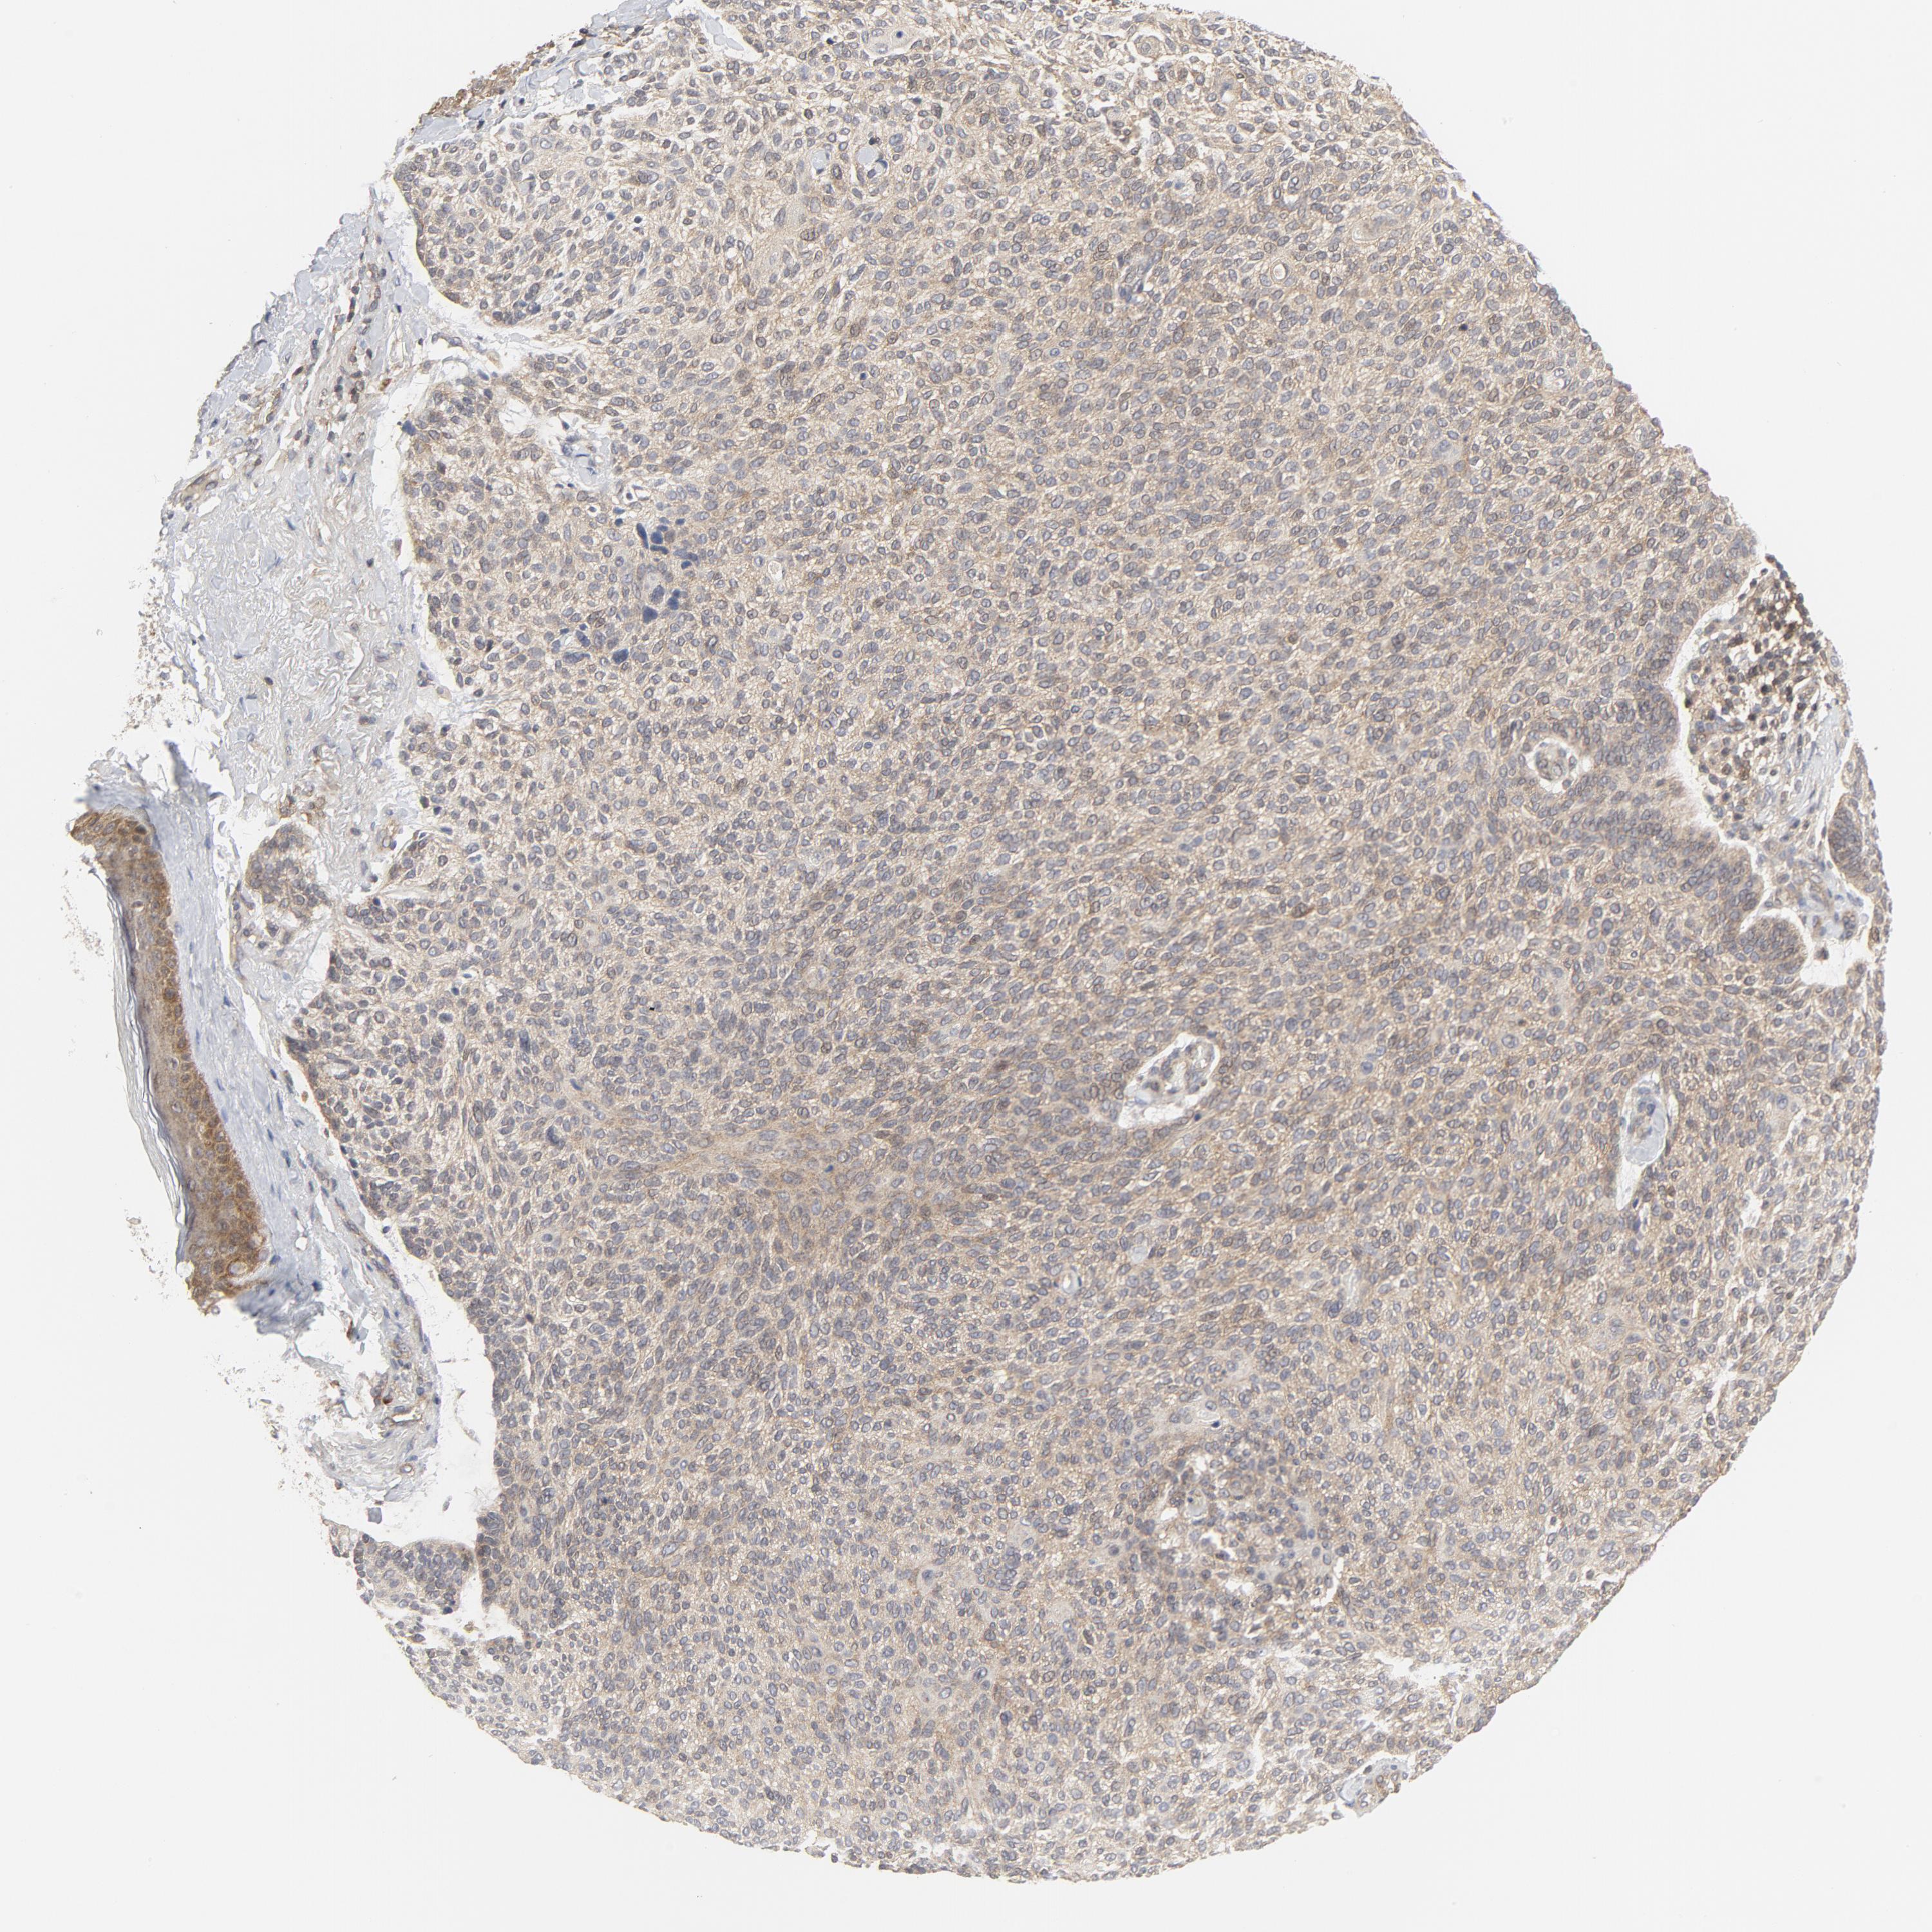

SKIN CANCER - Protein expressioni

A mouse-over function shows sample information and annotation data. Click on an image to view it in a full screen mode. Samples can be filtered based on level of antibody staining by selecting one or several of the following categories: high, medium, low and not detected. The assay and annotation is described here.

Antibody stainingi

Antibody staining in the annotated cell types in the current human tissue is reported as not detected, low, medium, or high, based on conventional immunohistochemistry profiling in selected tissues. This score is based on the combination of the staining intensity and fraction of stained cells.

Each image is clickable and will lead to virtual microscopy that enables deeper exploration of all samples and also displays staining intensity scores, fraction scores and subcellular localization as well as patient and tissue information for each sample.

Antibody HPA001633

Squamous cell carcinoma, NOS

Basal cell carcinoma